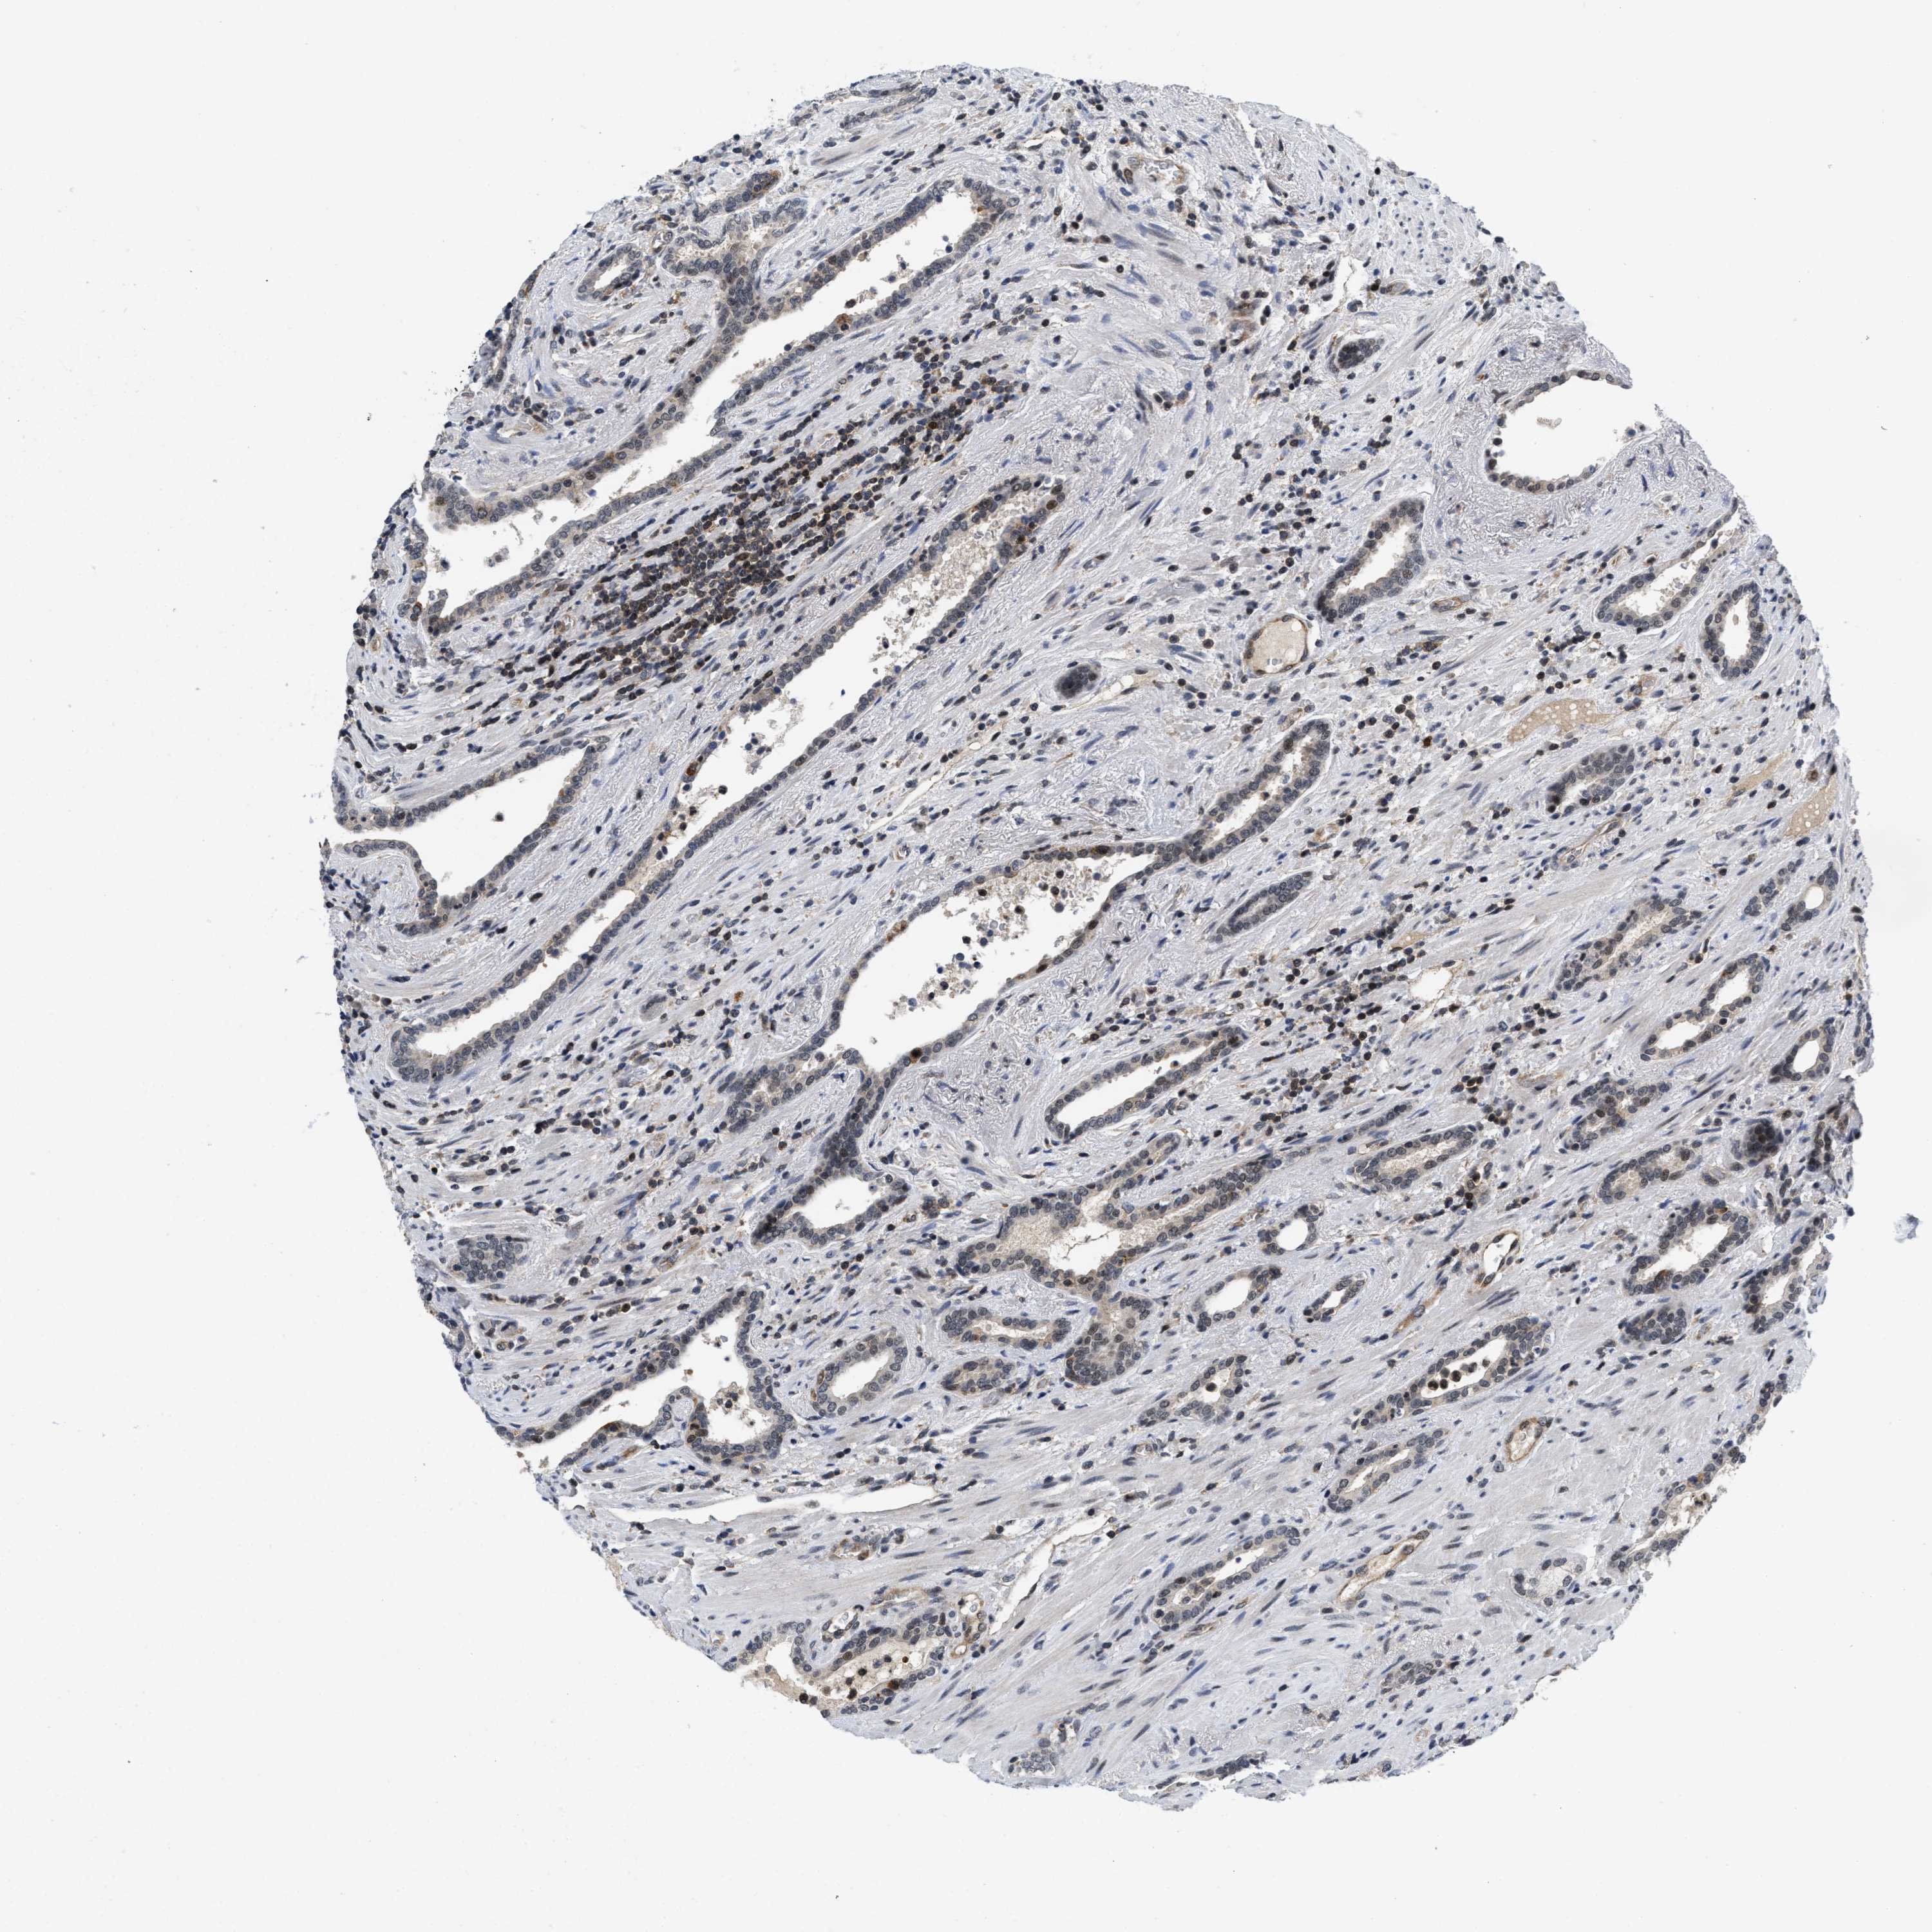

PROSTATE CANCER - Protein expressioni

A mouse-over function shows sample information and annotation data. Click on an image to view it in a full screen mode. Samples can be filtered based on level of antibody staining by selecting one or several of the following categories: high, medium, low and not detected. The assay and annotation is described here.

Note that samples used for immunohistochemistry by the Human Protein Atlas do not correspond to samples in the TCGA dataset.

Antibody stainingi

Antibody staining in the annotated cell types in the current human tissue is reported as not detected, low, medium, or high, based on conventional immunohistochemistry profiling in selected tissues. This score is based on the combination of the staining intensity and fraction of stained cells.

Each image is clickable and will lead to virtual microscopy that enables deeper exploration of all samples and also displays staining intensity scores, fraction scores and subcellular localization as well as patient and tissue information for each sample.

Antibody HPA001275

Antibody CAB017442

Staining

High

Medium

Low

Not detected

Intensity

Strong

Moderate

Weak

Negative

Quantity

>75%

75%-25%

<25%

None

Location

Nuclear

Cytoplasmic/membranous

Cytoplasmic/membranous,nuclear

Adenocarcinoma, Medium grade

Adenocarcinoma, Low grade

Adenocarcinoma, High grade